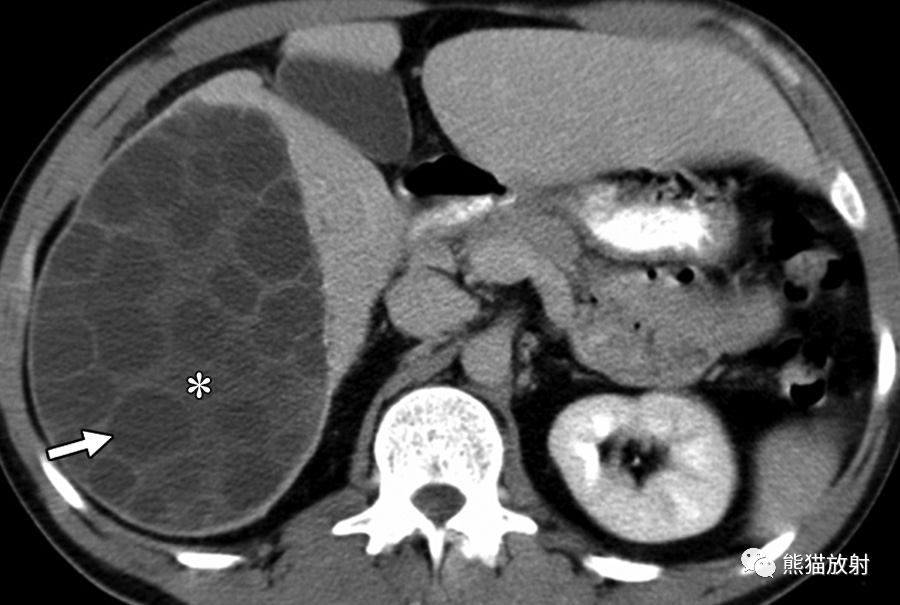

24岁男性,HIV感染患者,盗汗、发热,播散性结核感染。对比增强CT显示肝脏(黑箭)和脾(箭头)实质内多发微小低密度病变,腹膜后多发增大淋巴结(白箭)。

6岁男孩,肝巴尔通体病,被猫抓伤后发热3周。轴位增强CT图像显示多个低密度肝结节(箭)及门静脉周围增大淋巴结(箭头)。这些病变与转移瘤鉴别困难。然而,在无已知恶性肿瘤的免疫功能正常的年轻患者中观察到多发性肝脏病变应考虑到有肝巴尔通体病的可能。

巴尔通体病(猫抓病)是由巴尔通体引起的感染,该革兰氏阴性菌通过猫抓或咬伤引入人类宿主,最常影响儿童和年轻成人。猫抓或咬伤后1-3周开始出现症状,受伤部位近端出现疼痛性淋巴结肿大和发热。在无淋巴结肿大的情况下可发生内脏受累,表现为不明原因的发热。巴尔通体病的诊断可通过血清学试验、PCR试验或活检证实。播散性感染见于5%-10%的病例 。肝巴尔通体病的特征是多发性坏死性肉芽肿,范围为3-30mm,伴或不伴肝肿大。